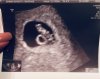

Hej, wpadam tylko zameldować, ze jestem po wizycie. Serduszko bije ❤️ Fasolka ma całe 0.96cm i wszystko póki co jest świetnie. Założył mi kartę ciąży i zaprosił na wizytę 21 grudnia. Powiedział, ze jeśli fasolka będzie na tyle duża by zrobić usg prenatalne to od ręki zrobi a jak nie to za kolejne 2 tyg. Jestem szczęśliwa i w końcu mogę odetchnąć. :)

• IMG_7693.jpg

144 KB · Wyświetleń: 91